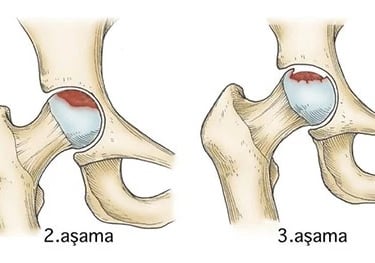

Evre II: Skleroz, kistik değişiklikler. Belirgin ağrı. (LR+ 10.0 - Röntgen tanısaldır)

Evre III: Crescent Sign (Hilal Belirtisi). Şiddetli ağrı, subkondral kırık ve çökme başlar. (LR+ - ∞ - Biyomekanik iflas)